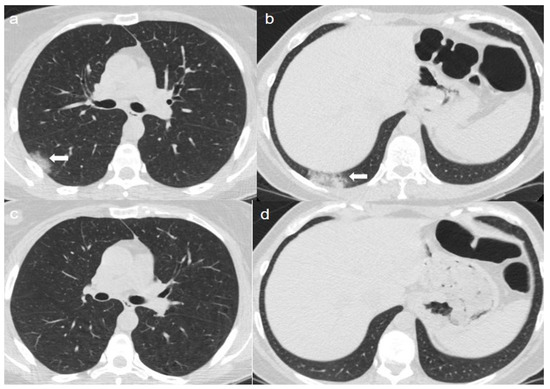

On admission, chest CT showed patchy areas of GGO with in upper lobes (Figure 4a,b), in the middle and left lower lobe (Figure 5a,b).

A CT at 4 months from the onset of symptoms showed the bilateral persistence of fibrotic stripes (Figure 4c,d and Figure 5c,d).

Figure 4. (a,b) CT shows patchy areas of GGO with in the upper lobes (arrows). (c,d) CT after 4 months from the onset of symptoms shows bilateral persistence of fibrotic stripes in upper lobes (thin arrows).

Figure 5. (a,b) CT shows patchy areas of GGO in the middle lobe (arrow in a) and in the left lower lobe (arrow in b). (c,d) CT after 4 months from the onset of symptoms shows bilateral persistence of fibrotic stripes in middle lobe (thin arrow in c) and in left lower lobe (thin arrows in d).